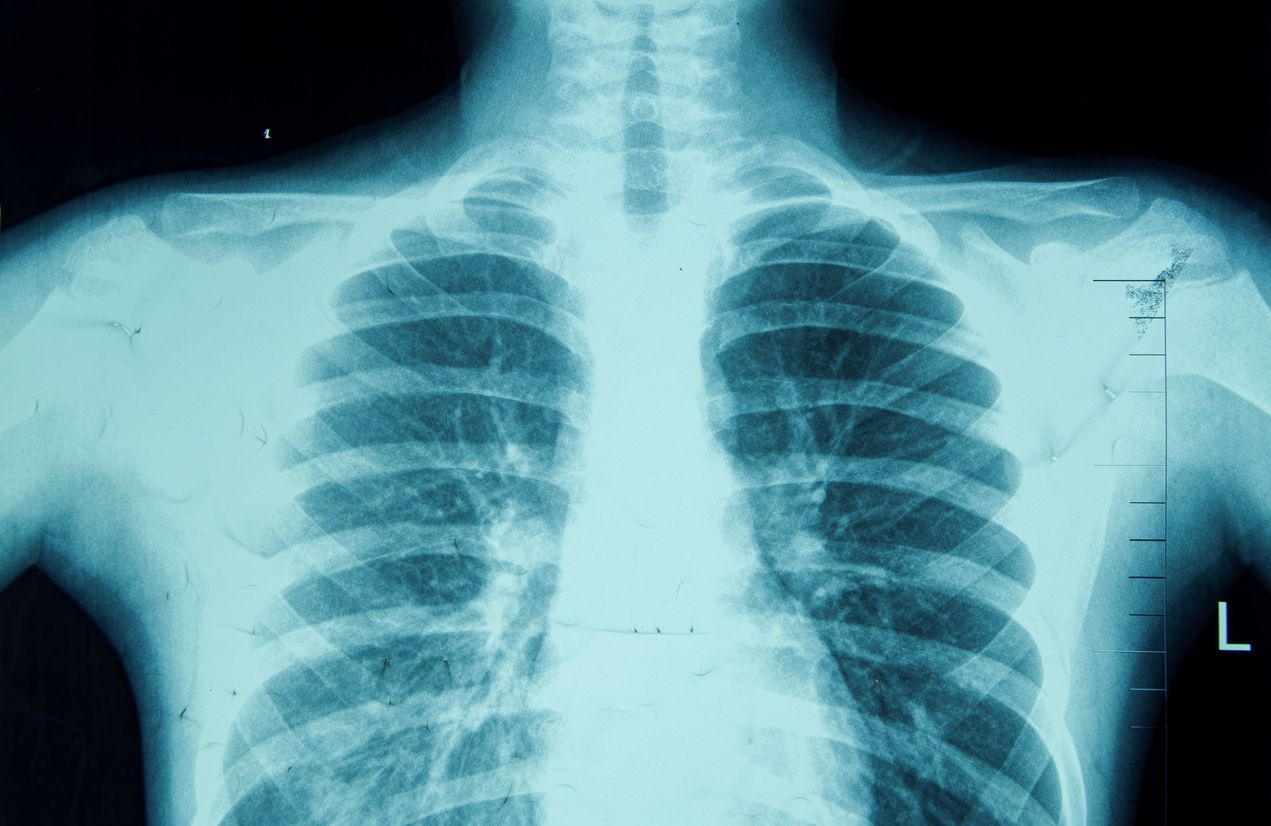

Gesunde Lunge

Anlässlich des Welt-Lungentages am 25. September spricht sich die Österreichische Gesellschaft für Pneumologie (ÖGP) erneut für ein umfassendes, österreichweites LungenGesundheitsVorsorgeProgramm (LGVP) aus. Ziel ist es, mittels Lungenkrebs-Screening sowohl Lungenkarzinome als auch andere Erkrankungen der Atemwege deutlich früher zu erkennen und behandeln sowie gleichzeitig präventive Maßnahmen systematisch zu stärken.

Lungenkrebs ist weltweit die tödlichste Krebserkrankung. Das Heimtückische ist, dass er lange Zeit über symptomlos verläuft und daher meist erst in einem schwer behandelbaren Spätstadium entdeckt wird. Zwar wird das Bronchuskarzinom generell immer besser behandelbar – moderne Therapien sind zunehmend ausgefeilter, weil maßgeschneiderter, zielgerichteter und damit auch effektiver und nebenwirkungsärmer – ihr Potenzial entfalten sie jedoch am wirkungsvollsten, wenn sie früh zum Einsatz kommen. Je später Lungenkrebs erkannt wird, desto eingeschränkter sind die Behandlungsoptionen und desto ungünstiger ist die Prognose.